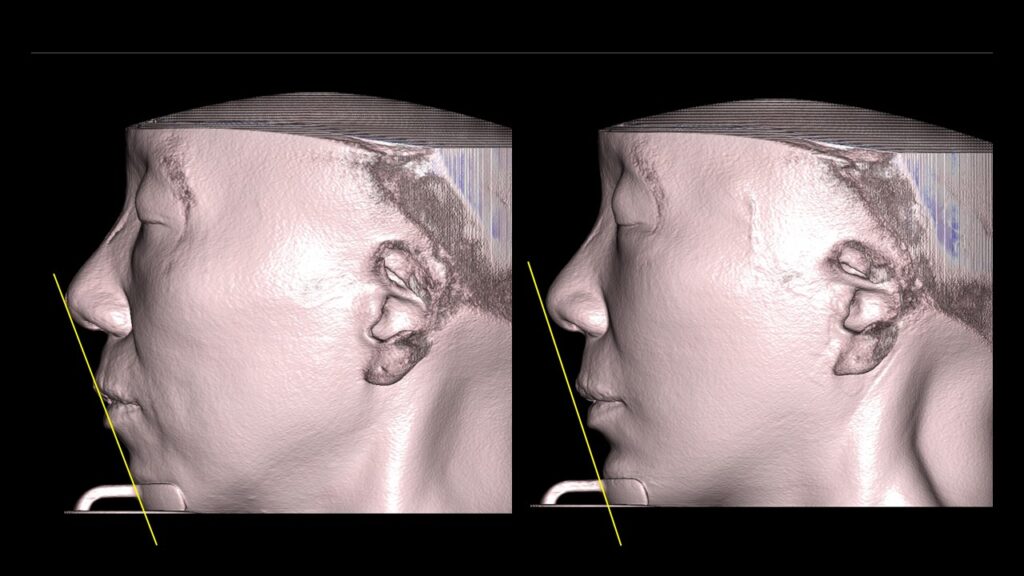

4. Case Studies (3DCT & Medical Photos)

-

Case 1: (Zygoma Reduction + Face Lift) 1-year post-op shows a significant reduction in mid-face width and improvement in nasolabial folds.

-

Case 2: (Zygoma + Chin Advancement + Face Lift + Brow Lift) Dramatic improvement in the side profile and double chin within just 1 month.